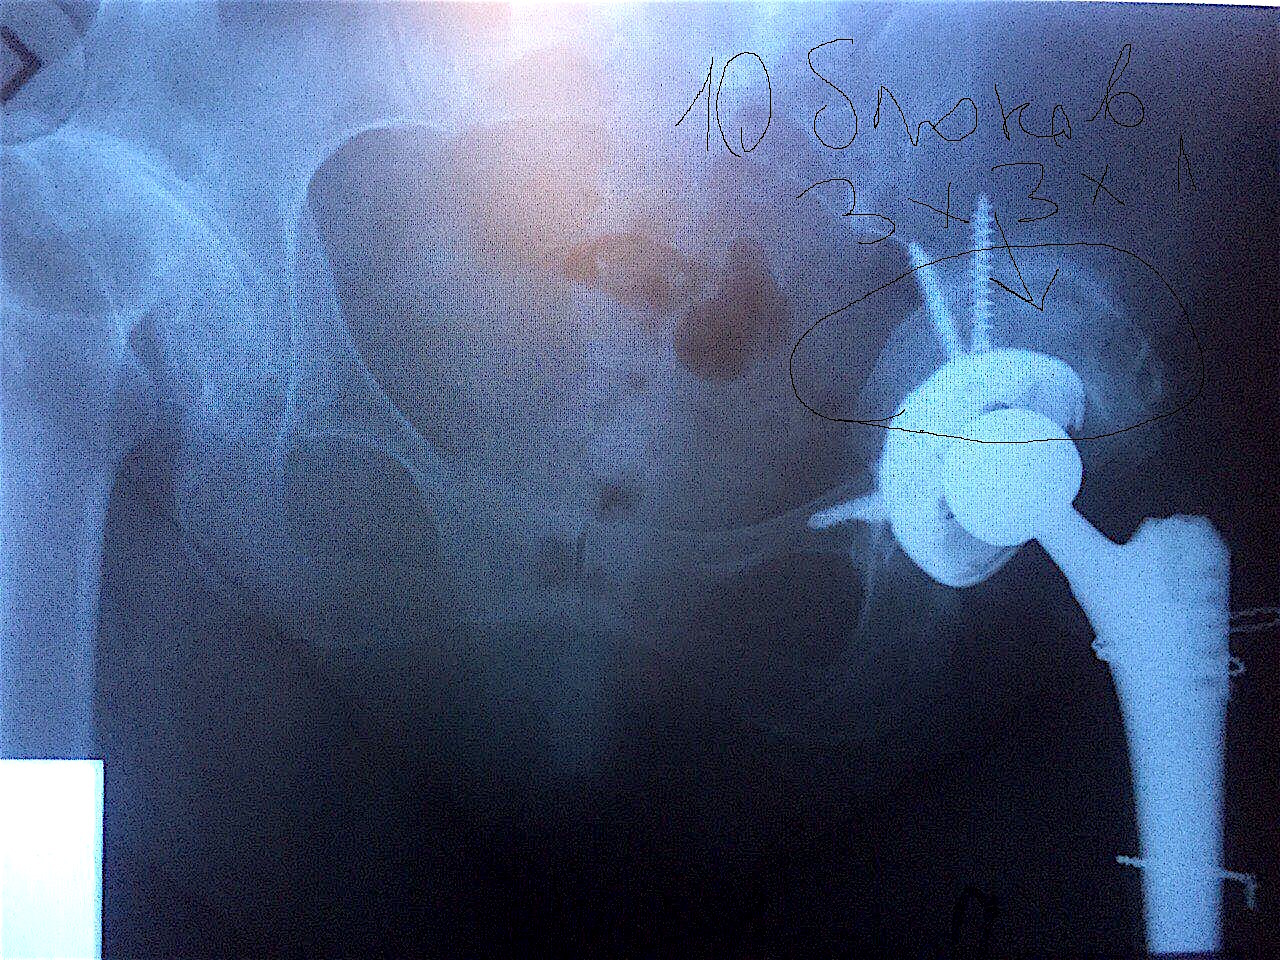

Сделано тотальное эндопротезирование левого тазобедренного сустава с компенсацией дефицита вертлужной впадины костным аллотрансплантатом «Лиопласт» (в количестве 10 шт. губчатых блоков 3х3х1 см).

Результат через 7 месяцев после операций